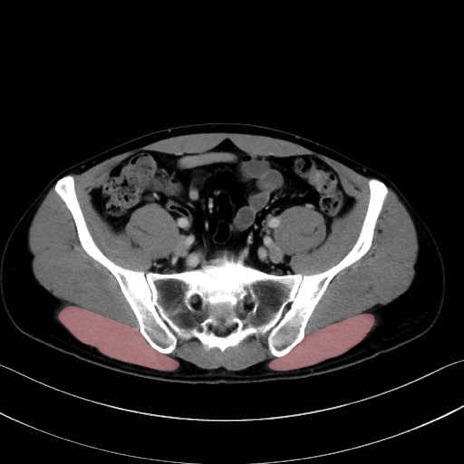

大殿筋 (Gluteus maximus)